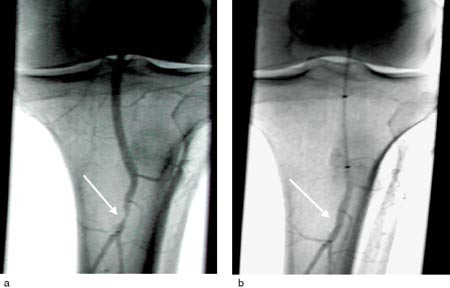

Totalt ble det utført 127 prosedyrer. Ved de fleste ble flere lesjoner behandlet. Nesten alle pasientene hadde karlesjoner (stenoser og okklusjoner) på flere nivåer, og hos mange ble også mer proksimalt beliggende lesjoner behandlet samtidig. Leggarteriene ble behandlet hos 54 pasienter (61 %) (fig 2). Okklusjoner >= 3 cm lengde ble behandlet ved 57 prosedyrer.

Subintimal PTA (11) var nødvendig i ni tilfeller for å oppnå rekanalisering. I 17 tilfeller hvor utredningen avslørte utbredte okklusjoner, ble det gitt trombolytisk behandling (r-tPA) med aspirasjon og påfølgende PTA. Stenter ble ikke brukt i a. poplitea eller leggarterier. Senere kontroll ved karkirurg eller generell kirurg ble utført som klinisk undersøkelse med registrering av symptomer, palpasjon av pulser og ev. måling av ankel-arm-indeks.